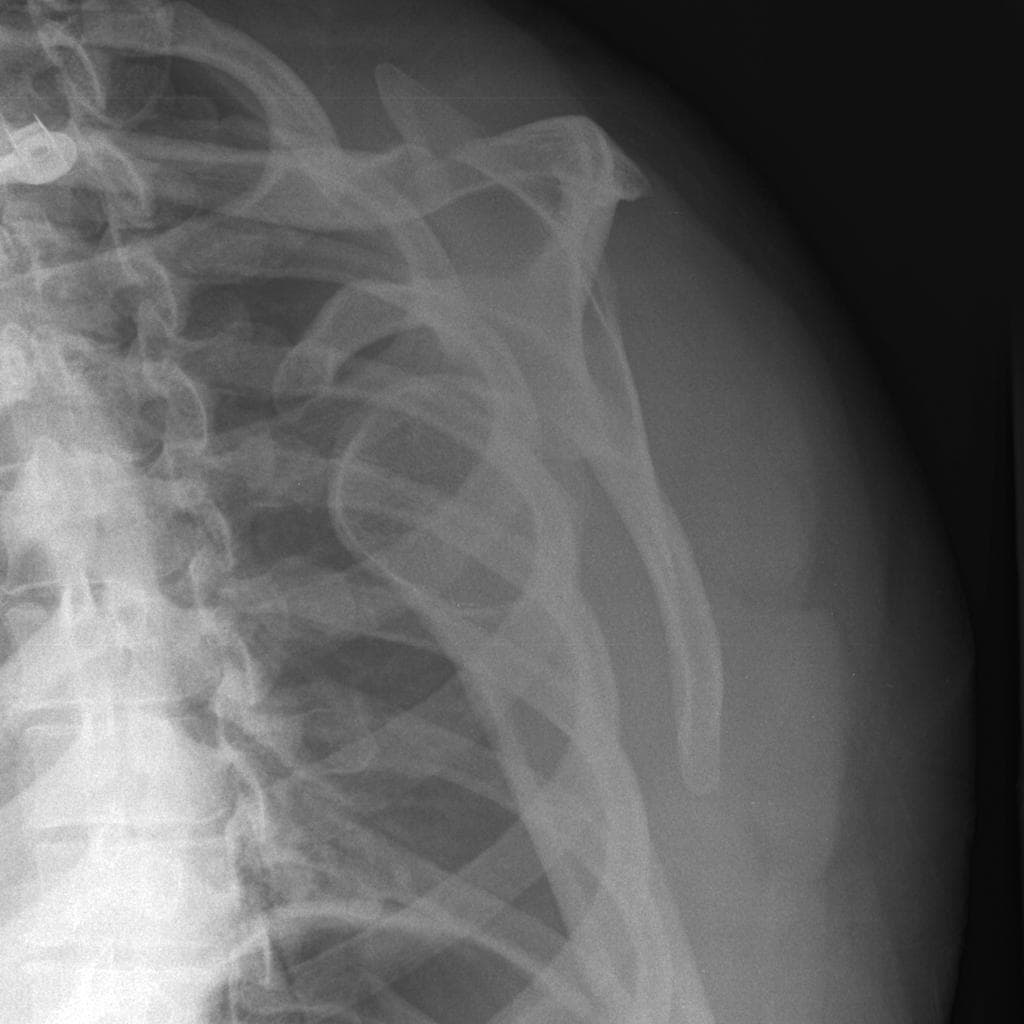

Trật khớp vai ra trước. Trục khớp ổ chảo - cánh tay bình thường. Không thấy trật khớp. THẢO LUẬN: Hình ảnh X-quang khớp vai phải cho thấy tình trạng trật khớp ra trước, đã được nắn chỉnh thành công.

Trật khớp vai ra trước thường xảy ra sau khi ngã với cánh tay ở tư thế giang và xoay ngoài. Chỏm xương cánh tay bị di lệch ra trước, vào trong và thường là xuống dưới so với ổ chảo. Đánh giá X-quang có vai trò quan trọng không chỉ để chẩn đoán mà còn để xác định các tổn thương xương đi kèm có thể ảnh hưởng đến việc điều trị và độ vững của khớp.